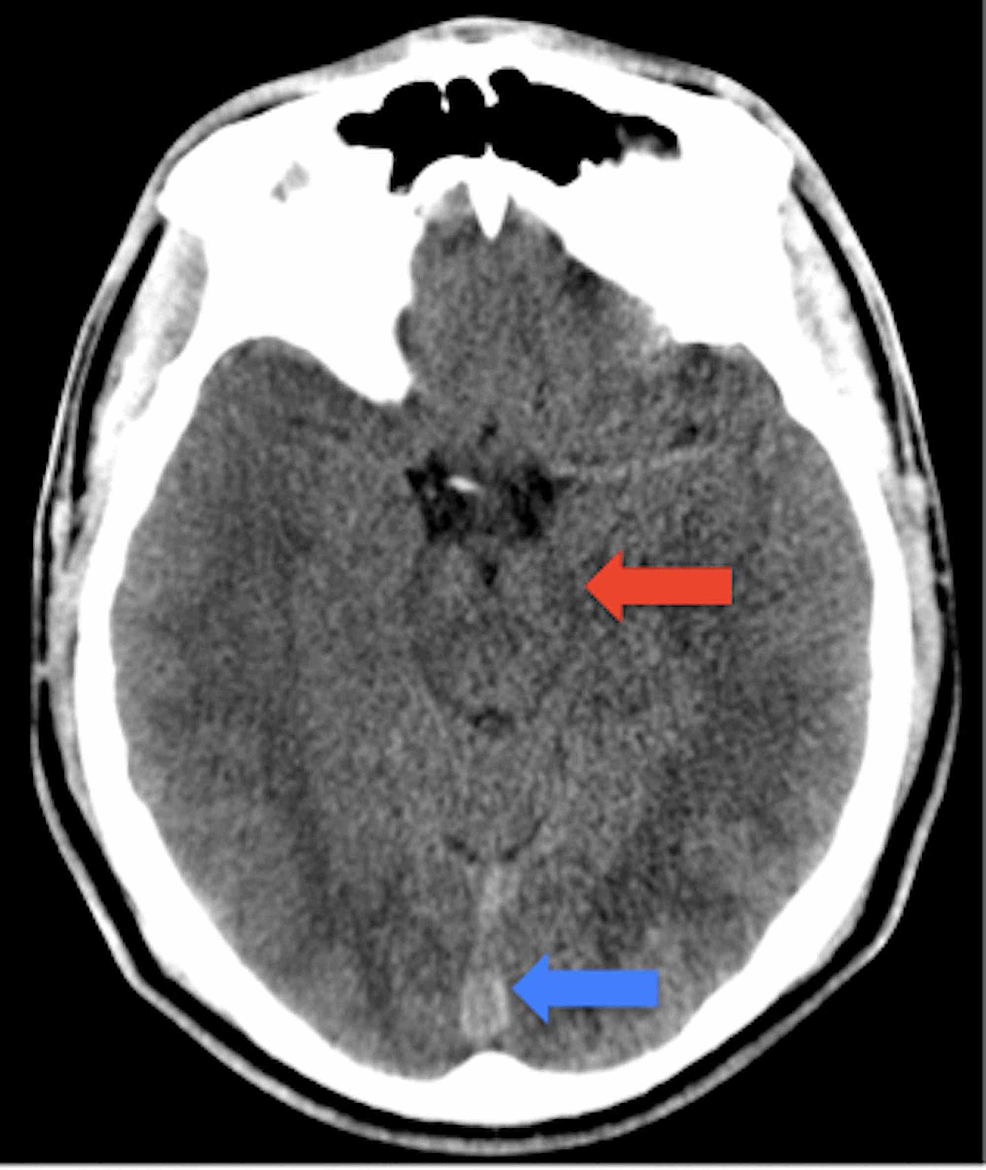

Ct Scan For Concussion. this means an imaging technology such as magnetic resonance imaging (mri) or computed tomography (ct) that can diagnose a severe traumatic brain injury (tbi), isn't a viable way to diagnose a concussion. Find out about the treatment options, including medications, surgery and rehabilitation, for different types of tbi. learn what a concussion is and how ct scans can help diagnose and exclude more serious injuries after a head. The study, published in jama. Find out how to interpret the results. several assessment devices to help guide decisions about obtaining a ct scan (e.g., banyon brain trauma indicator, 24 brainscope, 25. a ct scan may be indicated when it is likely a concussion requires immediate surgical intervention (surgery). learn how doctors use ct scan and other imaging tests to diagnose traumatic brain injury (tbi) and monitor its severity. learn about different concussion tests that assess your brain function after a head injury.